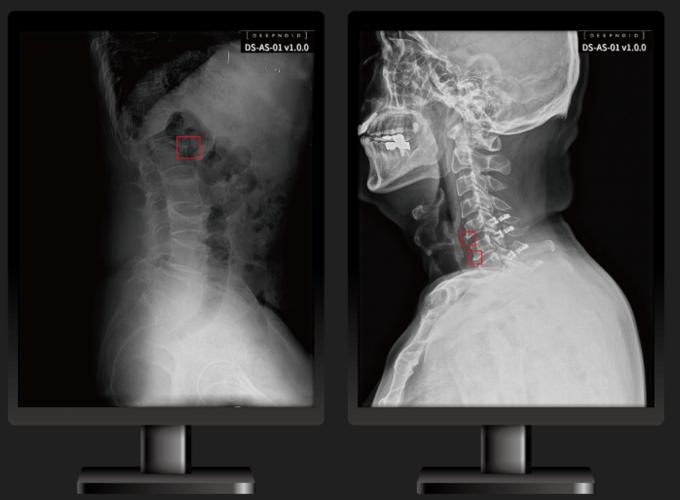

이번에 식약처 인증을 획득한 제품은 척추 관절병 등의 진료를 보조하는 '딥스파인(DEEP:SPINE, 모델명 DS-AS-01)'이다.

딥스파인은 척추 엑스레이(X-ray) 영상을 입력하면 학습된 모델이 이를 자동으로 분석해 척추 질환을 조기에 발견할 수 있도록 결과를 출력한다.

딥노이드가 식약처 인허가를 받은 의료영상분석 소프트웨어는 흉부의 이상(폐경화, 기흉)을 검출해 의료인의 진단을 보조하는 딥체스트(DEEP:CHEST)와 뇌신경두경부위 이상(뇌동맥류 등)을 검출하는 딥뉴로(DEEP:NEURO), 척추 이상(압박골절, 측만의 각도, 추간판 이상)을 찾아내는 딥스파인(DEEP:SPINE) 등이 있다.